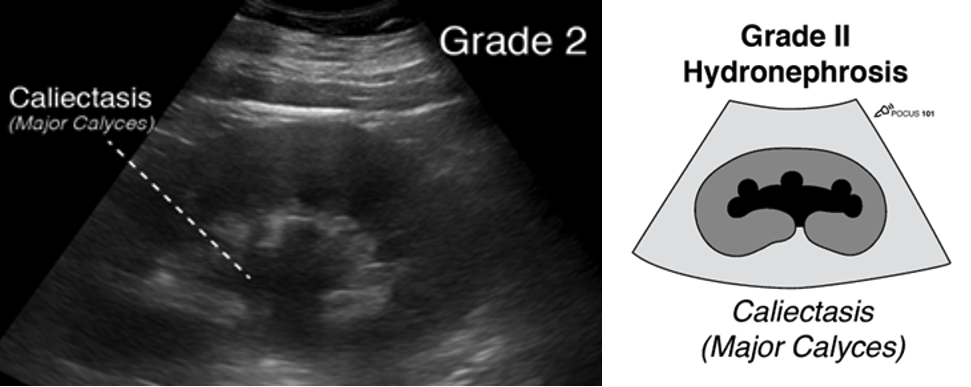

The PSAX view provides a cross-sectional image of the LV, allowing simultaneous visualization of multiple walls. It is the preferred view for global assessment of LVfx and RWMAs. This view is useful for assessing wall motion across the anterior, lateral, posterior, inferior, and septal segments, all seen in a single plane at multiple levels (basal, mid, apical) (figure 11).

Figure 11. PSAX at the mid-papillary level with left ventricular walls labeled.